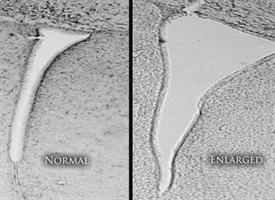

In one group of mice, the brains were examined 24 hours after the final pollution exposure. In all of those mice, inflammation was rampant throughout the brain, and the lateral ventricles -- chambers on each side of the brain that contain cerebrospinal fluid -- were enlarged two-to-three times their normal size.

Ventricles. Credit: University of Rochester.

“When we looked closely at the ventricles, we could see that the white matter that normally surrounds them hadn’t fully developed,” said Cory-Slechta. “It appears that inflammation had damaged those brain cells and prevented that region of the brain from developing, and the ventricles simply expanded to fill the space.”